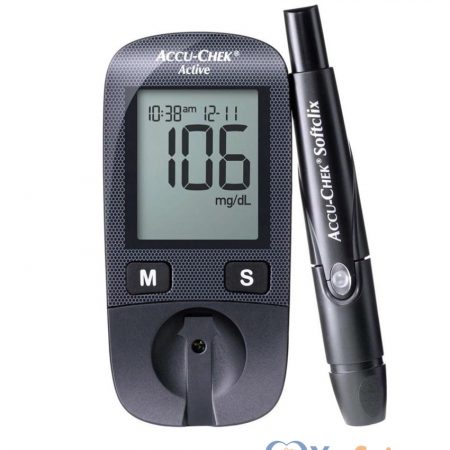

Máy đo đường huyết Accu-Chek Active do hãng Roche sản xuất. Dòng máy quý vị đang xem là dòng máy duy nhất trên thị trường được sản xuất tại Đức (Made in Germany) cho ra kết quả chính xác.

990.000 ₫